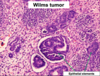

Wilms tumor (Nephroblastoma)

Malignant

2-5yo

Mutation of WT1 gene on short arm of Chromosome 11

Associated w/ WAGR syndrome: Wilms tumor, Aniridia (absent iris), Genital anomalies, mental Retardation & Denys-Drash (Wilms tumor, gonadal dygenesis, early-onset nephropathy w/ renal failure)

How does Wilms tumor clinically present?

What does prognosis depend on?

presents as abdominal mass and abdominal pain; hematuria, intestinal obstruction, hypertension; 5-10% bilateral

.

Prognosis depends on the degree of anaplasia of the tumor cells (defined by pleomorphism, hyperchromatism, abnormal mitoses), and the stage of the tumor at time of resection. Anaplastic tumors are more aggressive.

Gross pathologic features of Wilms tumor?

Nodular

Gray to tan-white

Soft, friable, fleshy

Wilms tumor Microscopic features (3)

- Triphasic pattern*

- Primitive blastema (small/dark undifferentiated cells)

- Epithelial component (abortive tubules/glomeruli)

- Stroma (Fibrous or myxoid patterns; may contain mesenchymal elements (cartilage, muscle, bone)

Wilms tumor microscopic features (3):

Triphasic pattern

- Primitive blastema (small/dark undifferentiated cells)

- Epithelial component (abortive tubules/glomeruli)

- Stroma (Fibrous or myxoid patterns; may contain mesenchymal elements (cartilage, muscle, bone)

Wilms Tumor

What is the significance of this in WIlms Tumor?

ANAPLASIA

Determines the Prognosis of Wilms tumor

- Pleomorphism, hyperchromatism, abnormal mitoses –> more aggresssive; higher resistance to chemotherapy

- Stage matters also w/ Prognosis*